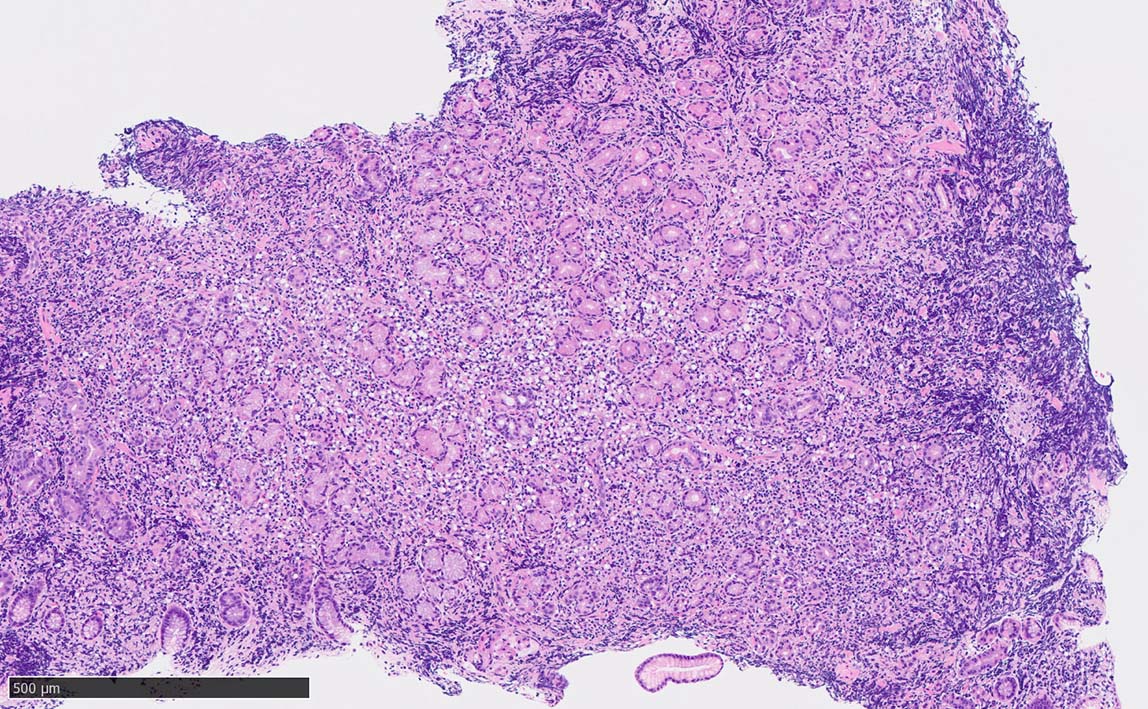

Signet-ring cell lymphoma of the stomach

60 year-old male. 胃生検組織

stomach biopsy, HE

腺窩上皮

x200 HE